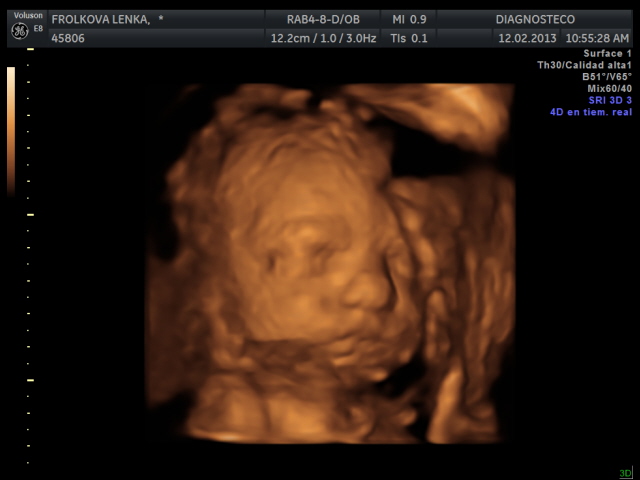

Manolito se nam vcera pretocil hlavickou nahoru a kouka na pater, takze nebyl moc videt, 4D utz zopakneme za 14 dni. Ale zatim mame nejakou tu fotecku a aji video, jen ne tak kvliatni.

Manolito uz vazi 1300 g a meri 36 cm. Ma cumacek po manzelovi a nosanek asi spis po me.

Leni Manolito je taky krásnoučkej